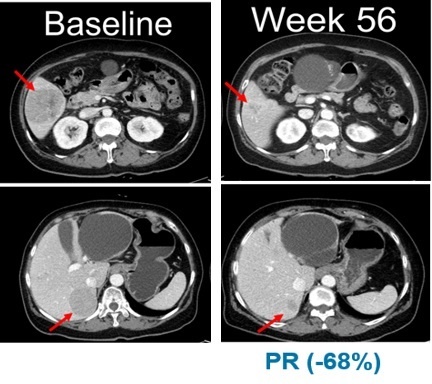

ÀÓ»ó ½ÃÀÛ Àü(Baseline,ÁÂÃø)°ú º§¹Ù¶óÆä´Õ Åõ¿© 56ÁÖ ÈÄ Èæ»öÁ¾ ȯÀÚÀÇ º¹ºÎ CT»çÁø

¶Ç ´Ù¸¥ ÆÄÆ®³Ê»ç Á¦³ÙÅØÀº ÁøÇ༺ °íÇü¾Ï ȯÀÚ¸¦ ´ë»óÀ¸·Î ‘º§¹Ù¶óÆä´Õ’°ú ÄÚºñ¸ÞƼ´Õ º´¿ë¿ä¹ýÀ» ÁøÇàÇÑ ¿¬±¸ °á°ú¸¦ ±¸¿¬À¸·Î ¹ßÇ¥Çß´Ù.

ÀûÀÀÁõ È®Àå ÀÓ»óÀÇ NRAS º¯ÀÌ Èæ»öÁ¾ ¿¬±¸¿¡¼­´Â ȯÀÚ 13¸í Áß 5¸íÀÌ ºÎºÐ¹ÝÀÀ(PR)À» º¸¿´À¸¸ç, ÃÖ°í¹ÝÀÀ·ü(BORR)Àº 38.5%·Î ³ªÅ¸³µ´Ù.